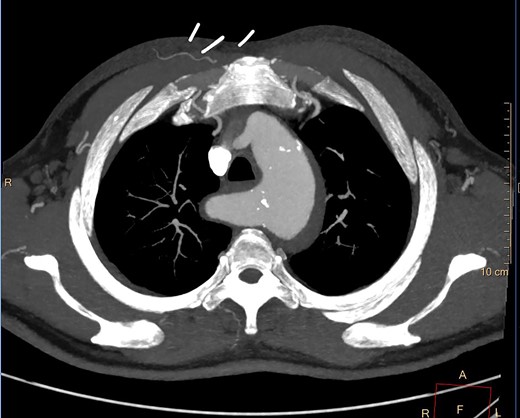

A computed tomography (CT) angiography was performed identifying a penetrating aortic ulcer (PAU) at the level of T11 with an intramural hematoma (IMH) extending to the inferior origin of the left subclavian artery origin (Fig. 1A). The IMH extended into ARSA with an associated KD (Fig. 1B). She was transferred immediately to the intensive care unit for anti-impulse therapy (dP/dt). The patient’s pain initially settled but then recurred during the admission and was refractory to blood pressure control.

(A) CT axial slice demonstrating PAU. (B) CT axial slice IMH seen extending into the KD.